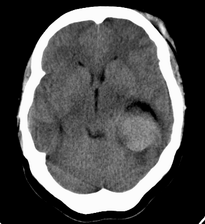

患者,女性,33岁,外伤检查发现,既往没有明显类似病史。

ct平扫见左侧脑室后角不规则形,边界不清的等密度肿块,肿瘤内有钙化,瘤周可见残存的脑室(低密度脑脊液影),考虑脉络脉丛乳头状瘤或室管膜瘤.

左侧侧脑室三角区占位性病变,其特点是平扫边界清、密度高、其内可见大块结节样的钙化,首先考虑起源于侧脑室三角区残余蛛网膜上皮的脑膜瘤可能性最大,无论是形态、密度、好发部位均符合脑膜瘤特点,建议增强进一步检查。

左侧脑室内软组织肿物,内部见多发不规则钙化,边界清楚锐利,有分叶。相应左侧脑室扩张。常见的不外乎3种病:室管膜瘤,脑膜瘤,脉络脉丛乳头状瘤。脑膜瘤分叶较少见,脉络脉丛乳头状瘤钙化较少见,因此,室管膜瘤可能性最大。

左侧脑室内见不规则略高密度团块影,边缘分叶,内见多发不规则钙化,病灶与侧脑室壁关系较为密切,左侧脑室扩大。考虑室管膜瘤可能性较大,其次为脑膜瘤,脉络丛乳头状瘤的可能性最小。

患者,女性,33岁,外伤检查发现,既往没有明显类似病史;

1、病灶除钙化外其它部分质均匀,无明显密度差别;

2、病灶界清,呈现膨胀性生长,对周围组织无明显浸润表现;

3、钙化部分范围较大,呈现大片状钙化;

4、病人为成年女性,无明显不适;

考虑:脑膜瘤;

鉴别诊断:室管膜瘤;脉络膜乳头状瘤;

平扫见左侧脑室三角区不规则形肿块,肿瘤内有钙化,瘤周可见残存的脑室(低密度脑脊液影),考虑脉络脉丛乳头状瘤或室管膜瘤.